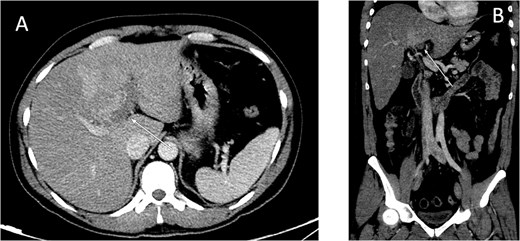

An ultrasound of the abdomen showed an impacted stone at the neck of the gallbladder with acute cholecystitis. The patient was admitted and started on IV antibiotics. He developed tachycardia reaching 110 bpm and had a high white blood cell count; therefore, the decision was made to proceed with a contrast-enhanced computed tomography (CT) scan, which showed evidence of acute cholecystitis and left PVT (Fig. 1). The medical team was consulted, and IV heparin without bolus was started. The gastroenterology team was consulted for his high bilirubin levels and advised for magnetic resonance cholangiopancreatography (MRCP), which was done the next day and confirmed the findings of left PVT (Fig. 2). MRCP also showed a micro perforation of the gallbladder and no biliary obstruction or stones (Fig. 3).

Contrast-enhanced CT scan of the abdomen: (A) axial cut; (B) coronal cut. Arrow indicates left portal vein thrombosis.